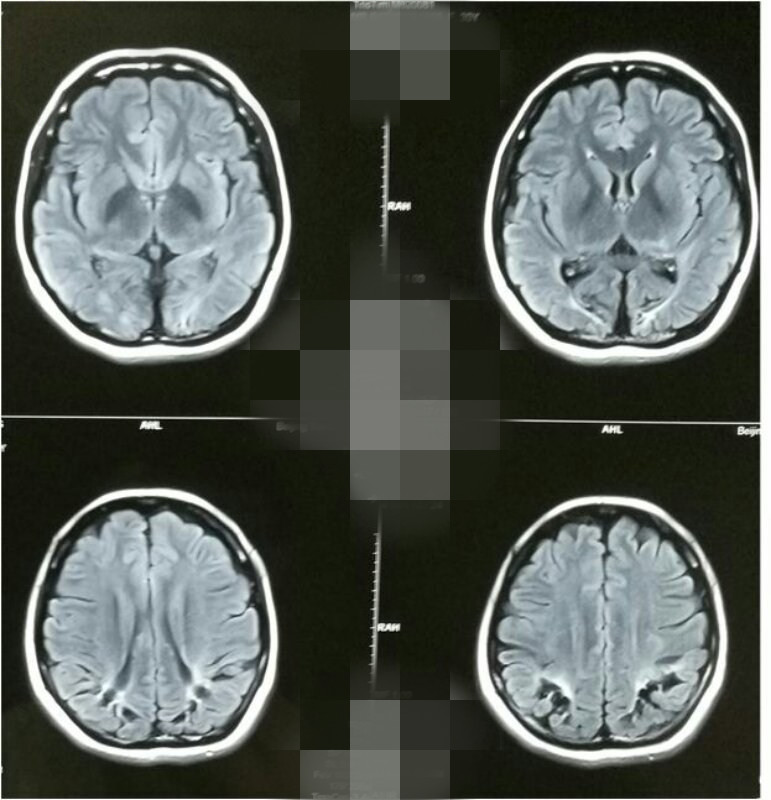

患者头颅MRI